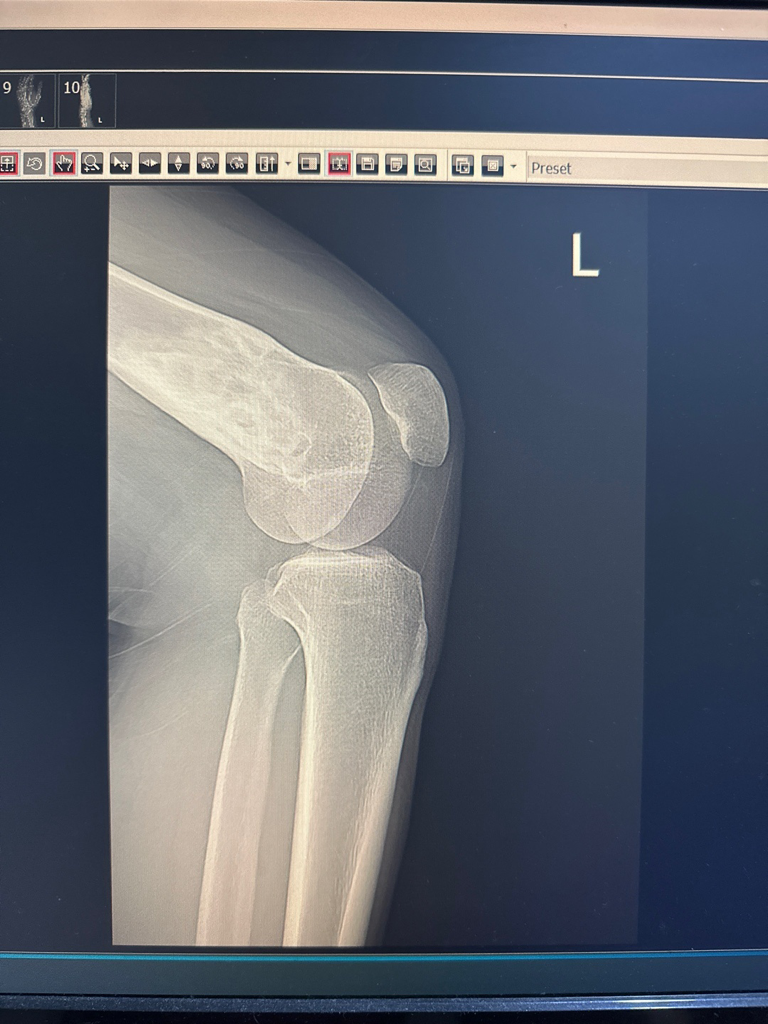

전공이 아니라 말씀드리기가 조심스럽지만 왼쪽 무릎 위쪽의 대퇴골에 덩이로 추정되는 것이 보이고 있어 추가검사를 요하는 것 같습니다. 골종양을 확인해야만 하는 상황이라 보입니다만 강력히 권한 정도가 아니라면 악성을 의심하시는 것 같지는 않습니다.